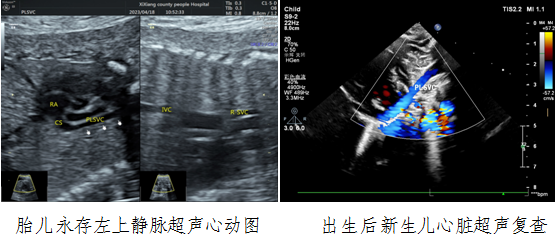

病例一,30岁,孕22w+,G2P1,既往产检未见胎儿心脏结构异常。2023年4月到西乡县医院例行常规产前超声检查,欧美视频

对口帮扶贾玄慧医生,超声发现胎儿存在先天大血管发育异常——永存左上腔静脉,指导孕妇进行产前咨询及产后随访。胎儿出生后1天,贾玄慧医生立即对该新生儿进行了心脏复查,结果确诊永存左上腔静脉诊断明确。